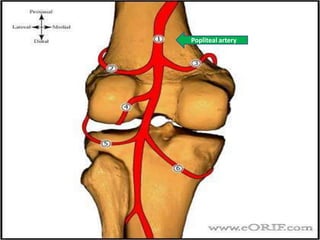

• Blood supply

– medial inferior genicular artery

– lateral inferior genicular artery

AnatomyPopliteal artery

Anatomy

ILG artery

IMG artery

Anatomy • Bloodsupply – medial inferior genicular artery – lateral inferior genicular artery

• #11 Blood supply 1-medial inferior genicular artery supplies peripheral 20-30% of medial meniscus 2-lateral inferior genicular artery supplies peripheral 10-25% of lateral meniscus central 75% receive nutrition through diffusion-This presents a problem when there is an injury to the meniscus, as the avascular areas tend not to heal without the essential nutrients supplied by blood vessels.